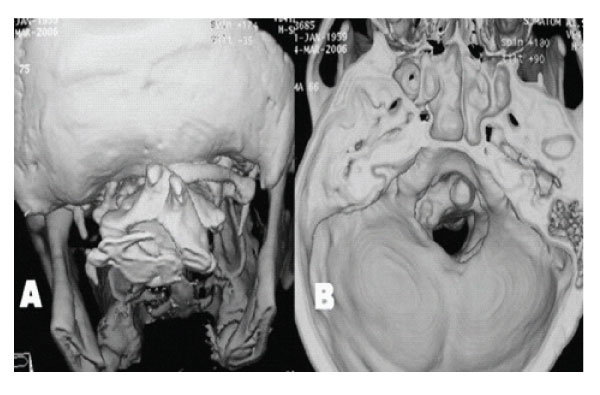

Figure 2: A: 3 D reconstructed CT scan showing assimilation of right posterior arch of Atlas, its right posterior arch can be seen. B: 3 D reconstructed CT scan showing inner aspect of posterior cranial fossa. A narrow, asymmetrical foramen magnum and shallow posterior fossa are seen.

X-ray examination disclosed no instability. Axial CT scans, three dimensional reconstructed CT scans and MRI showed anterior occipitalization of atlas, asymmetrical condyles with hypoplasia of left posterior part of the atlas, rightward deviation of odontoid process and C1-5 syringomyelia without tonsillar herniation [Figure- 1,2,3,4]. Posterior part of the axis was also asymmetrical. There was no appearance of basilar invagination although the tip of the axis was 2 mm superior to the foramen magnum level (McRae line).